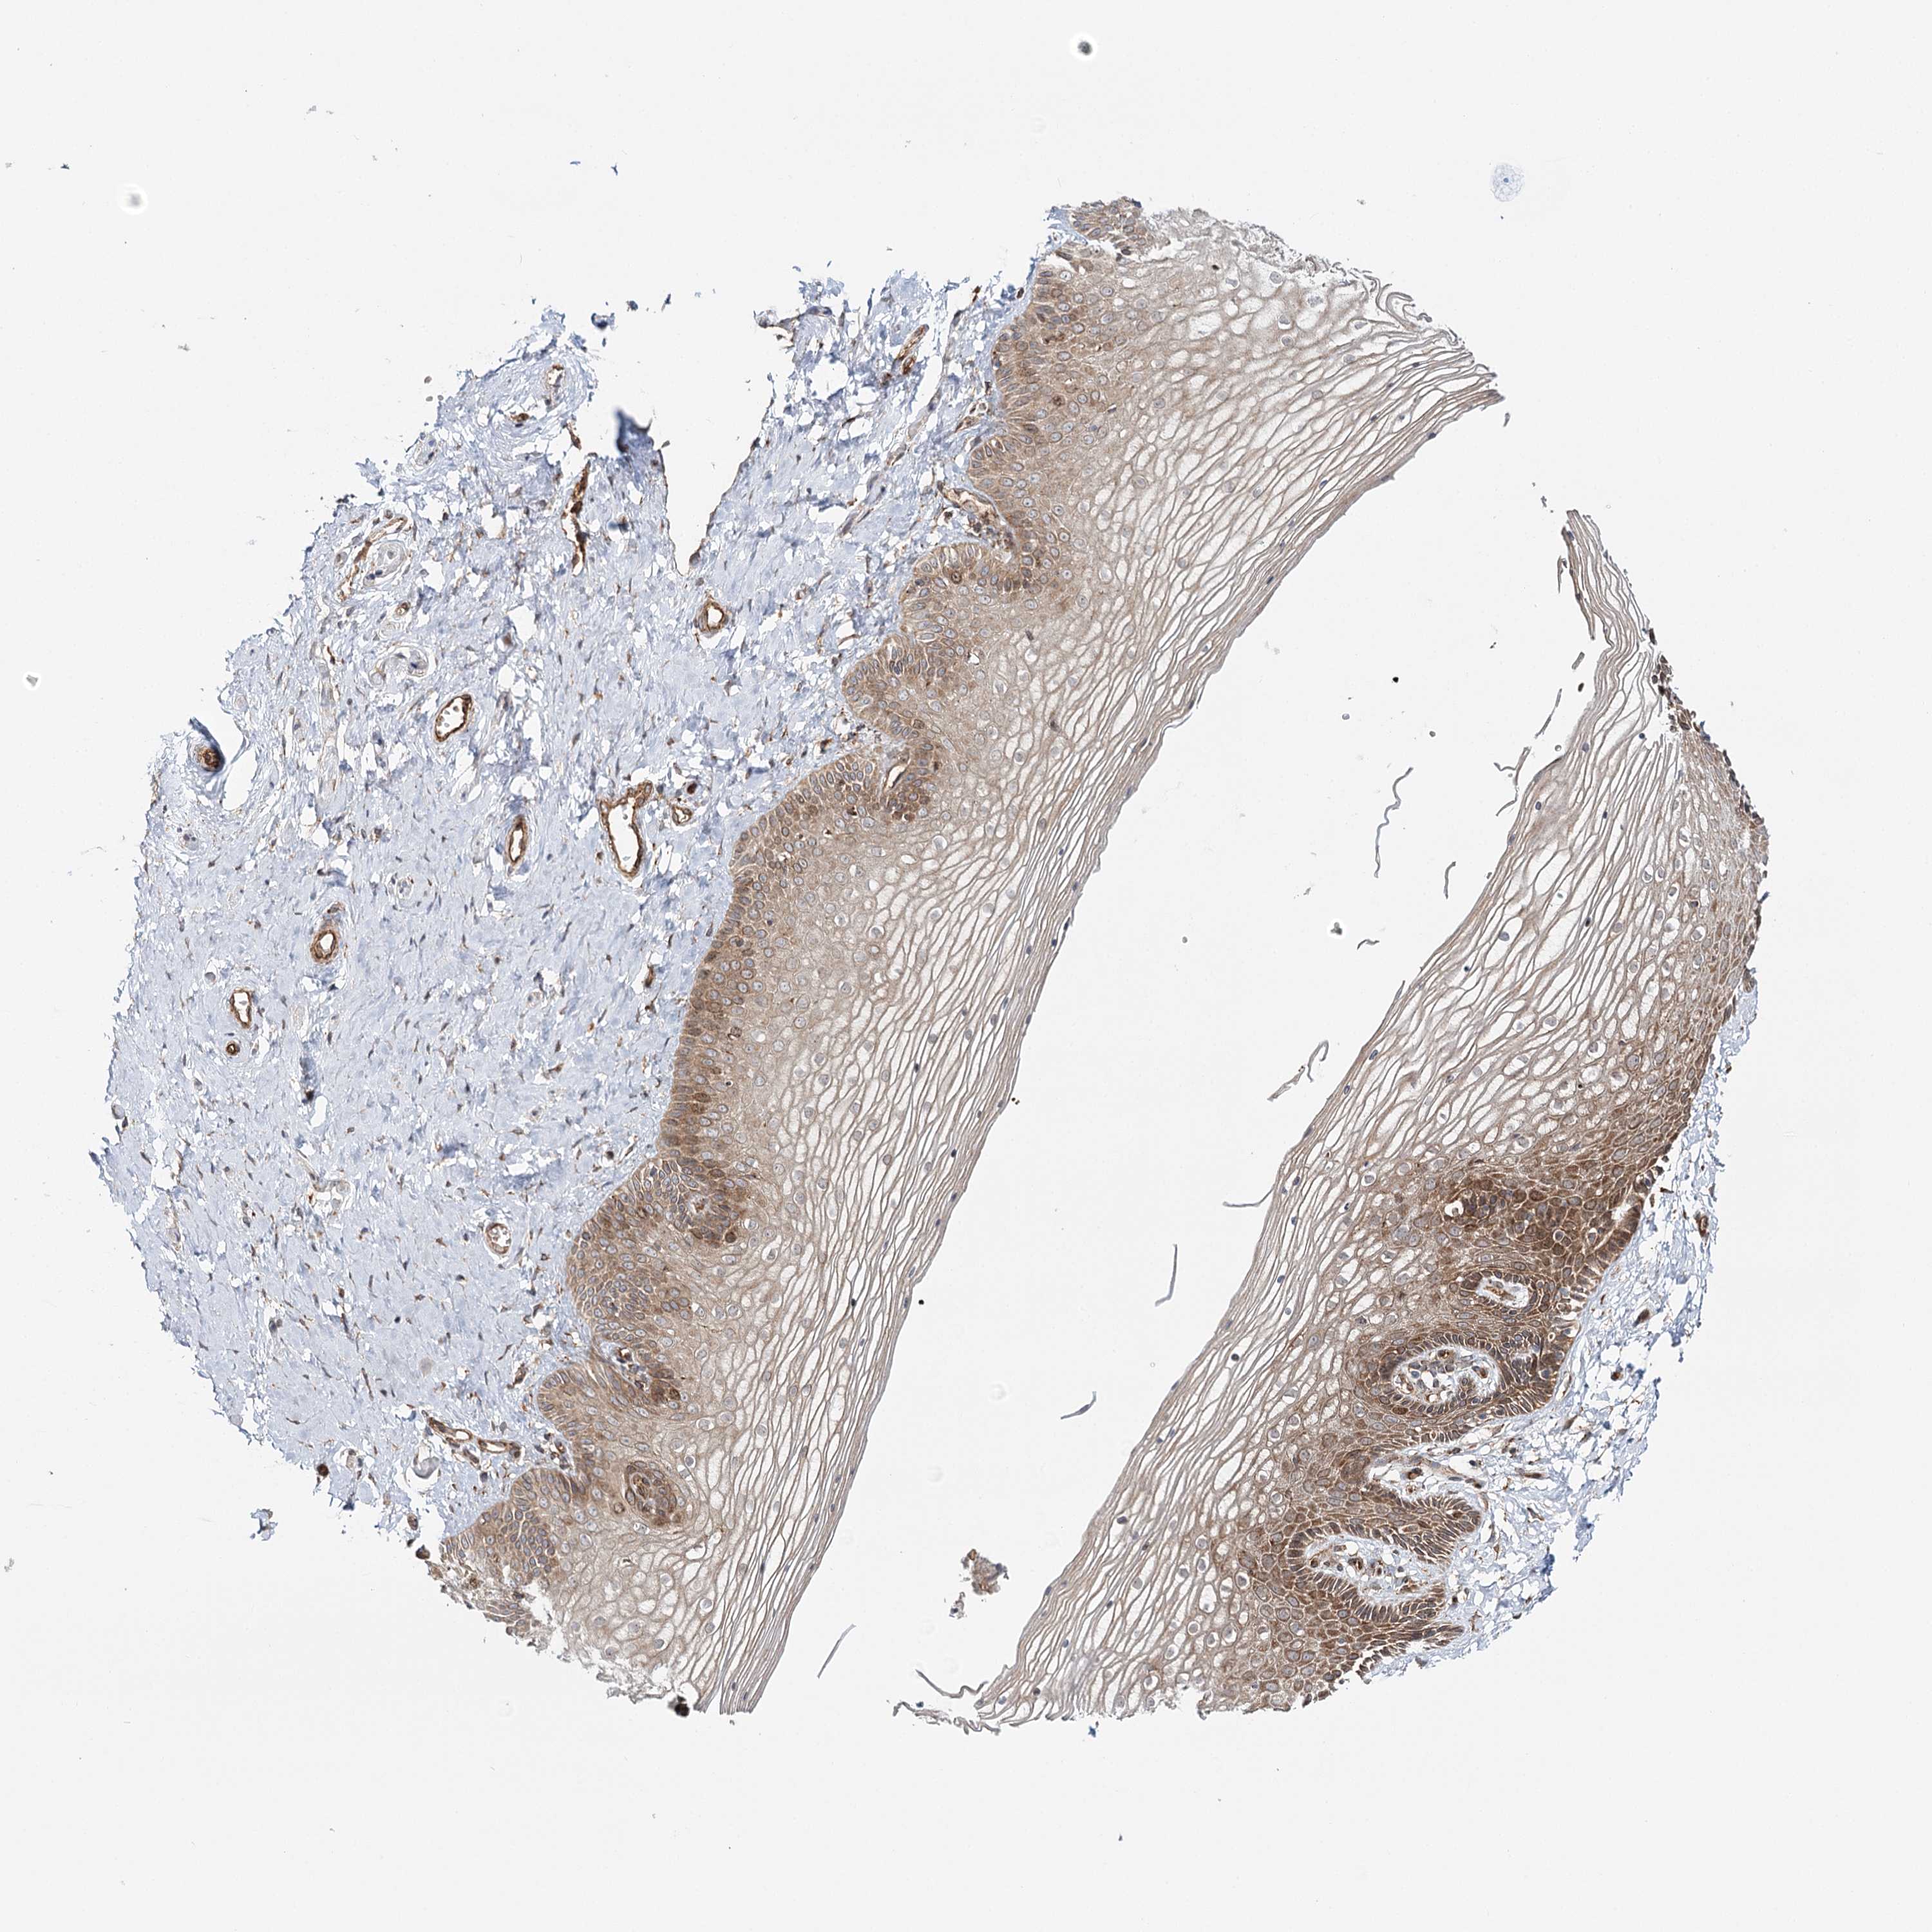

VAGINA - Antibody stainingi

Antibody staining in the annotated cell types in the current human tissue is reported as not detected, low, medium, or high, based on conventional immunohistochemistry profiling in selected tissues. This score is based on the combination of the staining intensity and fraction of stained cells.

Each image is clickable and will lead to virtual microscopy that enables deeper exploration of all samples and also displays staining intensity scores, fraction scores and subcellular localization as well as patient and tissue information for each sample.

Antibody CAB027355Antibody CAB037310

Squamous epithelial cells HighMedium